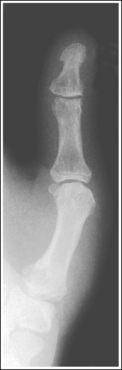

The digit of interest is in a lateral projection. The anterior aspect of the middle and proximal phalanges demonstrates midshaft concavity, and the posterior aspects of the phalanges show slight convexity.

• A lateral finger projection is accomplished by rotating the affected finger 90 degrees from the PA projection (Figure 4-11). Whether the hand is rotated internally or externally to obtain this goal depends on which direction will bring the finger closer to the IR. Typically, when the second and third fingers are imaged, the hand is rotated internally and, when the fourth and fifth fingers are imaged, the hand is rotated externally.

• Distinguishing lateral projection from rotated projection. To understand the difference between a truly lateral digit projection and a lateral projection that is rotated, study a finger skeleton in lateral and PA and AP oblique projections. Note how the midshaft concavity of the middle and proximal phalanges varies as the digit is rotated. In a lateral projection, the anterior aspect of these phalanges is concave, but the posterior aspect demonstrates slight convexity. In PA and AP oblique projections, both sides of the middle and proximal phalangeal midshafts demonstrate concavity, but the side toward which the anterior surface is rotated demonstrates a greater degree of concavity than the side toward which the posterior surface is rotated. The soft tissue width at either side of the phalanx also changes in the lateral and PA and AP oblique projections. More soft tissue is present on the side of the phalanges toward which the anterior surface is rotated (see Image 7).